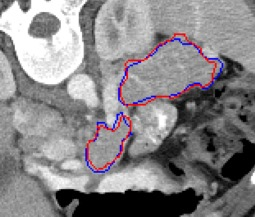

Automated segmentation in medical image analysis is a challenging task that requires a large amount of manually labeled data. However, most existing learning-based approaches usually suffer from limited manually annotated medical data, which poses a major practical problem for accurate and robust medical image segmentation. In addition, most existing semi-supervised approaches are usually not robust compared with the supervised counterparts, and also lack explicit modeling of geometric structure and semantic information, both of which limit the segmentation accuracy. In this work, we present SimCVD, a simple contrastive distillation framework that significantly advances state-of-the-art voxel-wise representation learning. We first describe an unsupervised training strategy, which takes two views of an input volume and predicts their signed distance maps of object boundaries in a contrastive objective, with only two independent dropout as mask. This simple approach works surprisingly well, performing on the same level as previous fully supervised methods with much less labeled data. We hypothesize that dropout can be viewed as a minimal form of data augmentation and makes the network robust to representation collapse. Then, we propose to perform structural distillation by distilling pair-wise similarities. We evaluate SimCVD on two popular datasets: the Left Atrial Segmentation Challenge (LA) and the NIH pancreas CT dataset. The results on the LA dataset demonstrate that, in two types of labeled ratios (i.e., 20% and 10%), SimCVD achieves an average Dice score of 90.85% and 89.03% respectively, a 0.91% and 2.22% improvement compared to previous best results. Our method can be trained in an end-to-end fashion, showing the promise of utilizing SimCVD as a general framework for downstream tasks, such as medical image synthesis and registration.